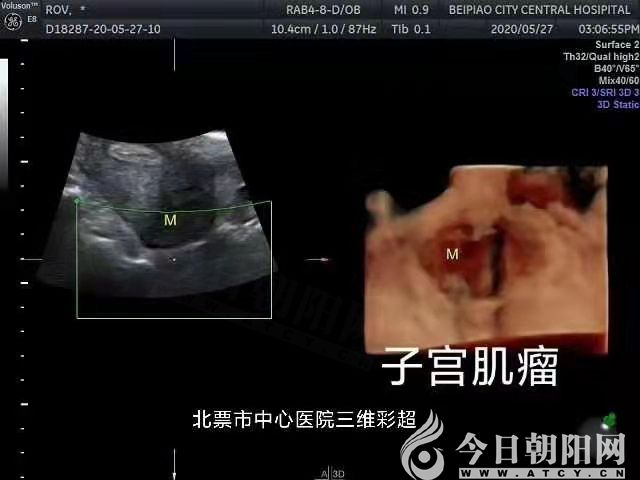

好消息!北票市中心醫(yī)院開展多項三維超聲檢查項目

近日,遼寧省北票市中心醫(yī)院超聲醫(yī)學(xué)科陸續(xù)開展了婦產(chǎn)、乳腺、甲狀腺等淺表器官及腹部、泌尿,腔內(nèi)等三維超聲檢查項目(咨詢電話:5080482),極大地滿足了城鄉(xiāng)廣大患者的就診需求,同時保證了臨床診療工作的順利有序進(jìn)行,提高了工作質(zhì)量和效率。

婦產(chǎn):子宮、附件、胎兒及其附屬物及腔內(nèi)超聲等;